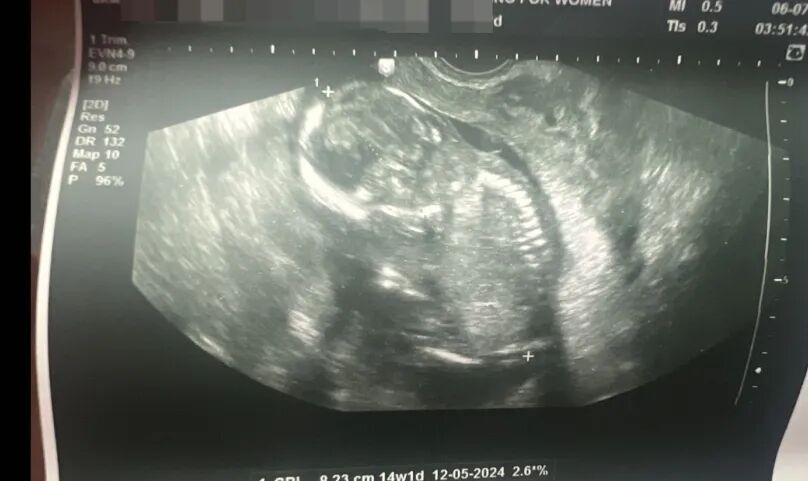

因为准爸爸的诊所非常的严格,在经历了一系列严格的筛选和最终的移植后,代母爱妈C成功怀孕,现在孕期已经到了十八周。准爸爸虽然远在千里之外,但他经常邮寄鲜花和小礼物来表达感激之情,整个家庭都充满了对即将到来大孙子都非常的期待和喜悦!